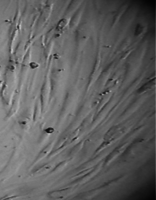

Вид монослоя и структура клеток не отличались от обычных в течение всех четырех суток наблюдения (рис. 32).

Количество поврежденных клеток было в пределах 2-5%.

Плотность монослоя на 2-е сутки в опыте составляла 1519 клеток/ммІ, в контроле - 1191 клеток/ммІ.

На четвертые сутки эксперимента клетки в контрольной чашке достигают плотности насыщения, которая равна для данной культуры 2020 клеток/ммІ.

Культура переходит в стационарную фазу роста, так как вступает в действие контактное торможение (нетрансформированные фибробласты в культуре растут в виде монослоя).